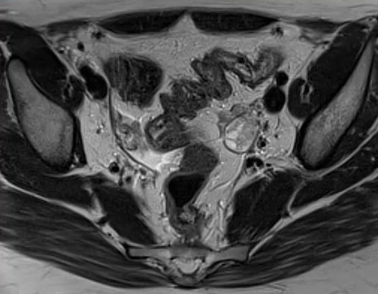

Endométriose

FELLAH L. - UCL

Année académique 2021-2022

Imagerie de la femme DES SPECIALITE